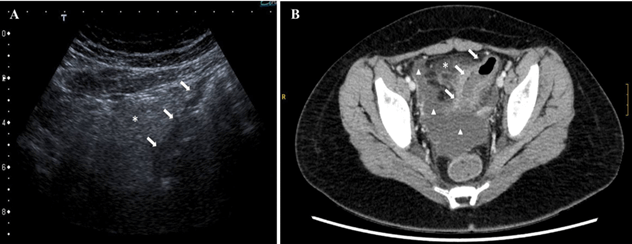

Figure 1: A) Abdominal US. Segmental wall thickening involving the sigmoid colon, concentric and uniform (white arrows). Hyperechoic mesenteric fat (asterisk), related to inflammatory changes. B) Abdominal contrast-enhanced CT (portal venous phase), axial image. Pronounced segmental concentric wall thickening of the sigmoid colon (white arrows). Severe surrounding fat stranding (asterisk) and moderate amount of free fluid (triangle).

The pain subsided, but the patient presented fever of 38ºC, diarrhea and pruritic macular rash of the trunk. On day 2 of admission, she presented sudden clinical worsening with lethargy, fever, tachycardia (150 beats per minute) with blood pressure at the lower limit of normal (systolic blood pressure 107 mm Hg/diastolic blood pressure 54 mm Hg), oliguria and mild metabolic acidosis. Given the suspicion of MIS-C with shock associated with COVID-19, she was admitted to the PICU. Electrocardiogram and echocardiography were normal. Laboratory results are summarized in (Table 1). Other etiology was ruled out with a full serology and body fluid cultures. The patient received vasopressor support (noradrenaline 0.1 mcg/kg/min), antibiotics for suspected abdominal bacterial co-infection (ceftriaxone 50 mg/kg/24h and metronidazole 10 mg/kg/8h), COVID-19 treatment (hydroxychloroquine 6.5 mg/kg/12h 4 doses; low-molecular-weight heparin 0.5 mg/kg/12h; vitamin K 10 mg/dose), and MIS-C treatment (interleukin-6 inhibitor (tocilizumab) 8 mg/kg/24h 1 dose; intravenous immune globulin 2 g/kg/24h 1 dose; methylprednisolone 2 mg/kg/24h 1 dose). The study was completed with abdominal computed tomography (CT) (Figures 1B, 2A & 2B). We observed radiologic signs of severe acute sigmoiditis, homogeneous splenomegaly of 140 mm and mild bilateral pleural effusion with passive atelectasis of lung parenchyma but no parenchymatous involvement characteristic of COVID-19 in the lower thorax included in the CT.

In our case, US revealed hyperechoic pelvic mesenteric fat related to inflammatory changes and concentric wall thickening of the sigmoid colon (Figure 1A). However, acute appendicitis could not be ruled out because the cecal appendix was not visible. CT performed after clinical worsening revealed marked concentric parietal thickening of sigmoid colon suggesting acute inflammatory-infectious sigmoiditis, increased density and trabeculation of adjacent and retroperitoneal fat, engorgement of the vasa recta (comb sign), lymph node swelling and a moderate amount of intra-abdominal fluid in relation to marked inflammatory changes; ileocecal appendix was normal (Figures 1B, 2A & 2B).